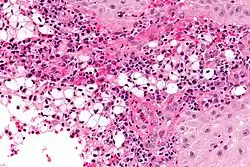

| Photogravure of rhinoscleroma from Wolkowitsch. | |

A positive culture in MacConkey agar is diagnostic, but cultures are only positive in 50–60% of cases. Diagnostic characteristics are most commonly found in the granulomatous stage and are described as being plasma cells with birefringent inclusions, Russell bodies, pseudoepitheliomatous hyperplasia, and groups of large vacuolated histiocytes containing Klebsiella rhinoscleromatis (Mikulicz cells).[2]